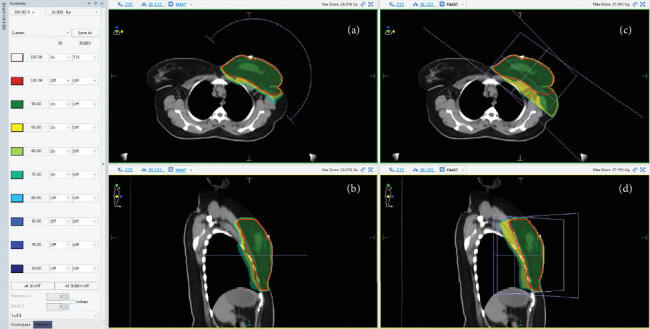

目的:本研究旨在比较前向IMRT (F-IMRT)和VMAT技术在通过Elekta主动呼吸协调器(ABC)系统使用低分割放疗辅助治疗左侧乳腺癌1周以上深度吸气屏气(DIBH)的效果。材料与方法:对26例患者分5段接受26 Gy (5.2 Gy/段)的治疗方案进行分析,然后再分5段进行10 Gy的电子增强。升压阶段被排除在比较之外。评估F-IMRT和VMAT计划的剂量至体积的95%、符合性指数(CI)、平均左肺剂量(MLLD)、左肺V8 Gy、平均心脏剂量(MHD)、心脏V1.5Gy和V7Gy、平均右乳剂量(MRBD)和平均右肺剂量(MRLD)。统计学分析采用Wilcoxon符号秩检验。结果:F-IMRT组和VMAT组的PTV覆盖率相似(95.83%比95.38%),但VMAT组的CI显著提高(1.31比1.04)。与VMAT相比,F-IMRT显著降低MLLD (4.55 Gy对5.95 Gy)和左肺V8Gy(18.78%对25.87%)。与VMAT相比,F-IMRT的MHD较低(1.79Gy对2.47Gy),心脏V1.5Gy显著降低(21.6%对54.4%),V7Gy在F-IMRT和VMAT之间无差异(5.04%对5.79%)。与VMAT相比,F-IMRT也导致较低的MRBD (0.62 Gy对2.4 Gy)和MRLD (0.38 Gy对1.8 Gy)。结论:F-IMRT提供了与VMAT相当的目标覆盖范围,同时在1周内显著减少了对心脏、肺和对侧乳房的辐射暴露,用于左侧乳腺癌DIBH和低分割治疗。鉴于其剂量学优势,F-IMRT应该是提高患者安全性和减少长期毒性的首选技术。

Objective: This study is aimed at comparing the forward IMRT (F-IMRT) and VMAT techniques in the adjuvant treatment of left-sided breast cancer using hypofractionated radiation over 1 week with deep inspiration breath hold (DIBH) via the Elekta Active Breathing Coordinator (ABC) system. Materials and Methods: Treatment plans for 26 patients receiving 26 Gy in five fractions (5.2 Gy/fraction), followed by a 10-Gy electron boost in five fractions, were analyzed. The boost phase was excluded from the comparison. F-IMRT and VMAT plans were evaluated for dose to 95% of the volume, conformity index (CI), mean left lung dose (MLLD), left lung V8 Gy, mean heart dose (MHD), heart V1.5Gy and V7Gy, mean right breast dose (MRBD), and mean right lung dose (MRLD). Statistical analysis was conducted using the Wilcoxon signed-rank test. Results: PTV coverage was similar in F-IMRT and VMAT arms (95.83% vs. 95.38%), but CI was significantly improved with VMAT (1.31 vs. 1.04). F-IMRT significantly reduced MLLD (4.55 Gy vs. 5.95 Gy) and left lung V8Gy (18.78% vs. 25.87%) when compared to VMAT. MHD was lower with F-IMRT (1.79Gy vs. 2.47Gy), with significantly reduced heart V1.5Gy (21.6% vs. 54.4%) when compared to VMAT, with V7Gy not different (5.04% vs. 5.79%) between F-IMRT and VMAT. F-IMRT also resulted in lower MRBD (0.62 Gy vs. 2.4 Gy) and MRLD (0.38 Gy vs. 1.8 Gy) when compared to VMAT. Conclusion: F-IMRT provides comparable target coverage to VMAT while significantly reducing radiation exposure to the heart, lungs, and contralateral breast for left-sided breast cancer treatment with DIBH and hypofractionation over 1 week. Given its dosimetric advantages, F-IMRT should be the preferred technique to enhance patient safety and minimize long-term toxicities.